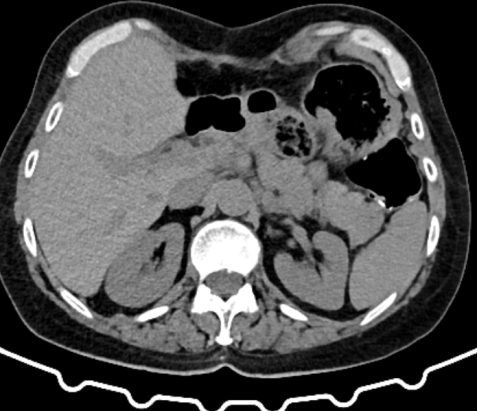

CT Scan. The gastric tumors are obvious (red arrow). Incidental finding right sided sizable renal cysts (blue arrow)